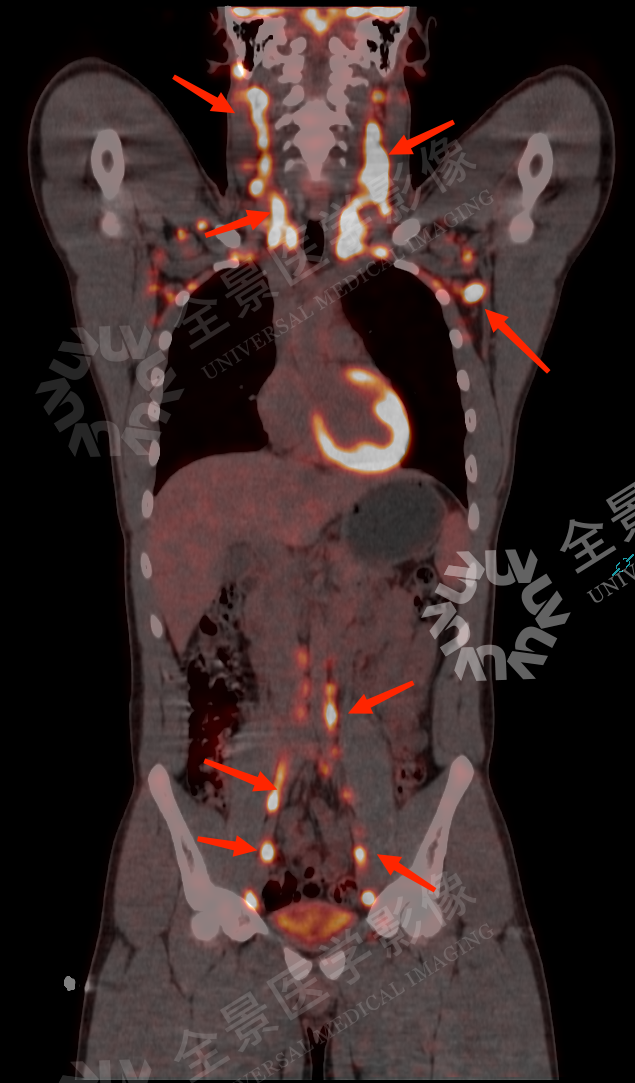

检查影像资料如下

PET/CT 显示:双侧颌下、颏下、颈部、锁骨上区、腋下、腹膜后区、盆腔髂血管旁、腹股沟区多发串珠状增大淋巴结,两上臂多发结节,FDG 代谢增高。